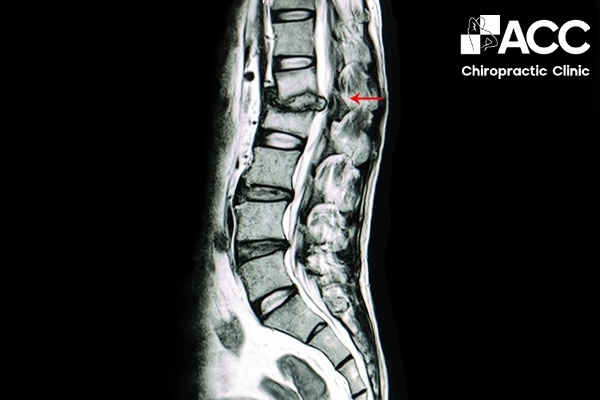

Người bệnh bị nhói sau lưng là bệnh gì? Đó có thể do bệnh nhân bị bệnh thoát vị đĩa đệm. Khi đĩa đệm tổn thương có thể đè lên các dây thần kinh gần đó, từ đó có thể gây đau tê ở vùng lưng, yếu cơ. Thoát vị đĩa đệm có thể xuất hiện ở bất cứ vị trí nào của lưng, lan dần một bên hoặc hai bên mông và chân.

Đĩa đệm phồng ra có thể lệch ra khỏi vị trí giữa các xương, gây áp lực lên dây thần kinh. Điều này khiến vị trí sau lưng bị đau nhói, khó cử động, một số trường hợp có thể dẫn đến đau thần kinh tọa.

Bị nhói sau lưng có thể là do đĩa đệm bị phình ra, gây chèn ép dây thần kinh gây đau nhói sau lưng.

Bác sĩ sẽ tiến hành thăm khám lâm sàng như hỏi tiền sử bệnh, quan sát dáng đi, tư thế đứng hoặc ngồi,… kết hợp với các phương pháp chẩn đoán hình ảnh để đánh giá chính xác tình trạng của người bệnh. Theo đó, bác sĩ có thể chỉ định:

- Xét nghiệm hình ảnh như chụp CT, chụp X-quang, MRI,… giúp bác sĩ xác định các chấn thương, tổn thương ở vùng lưng.